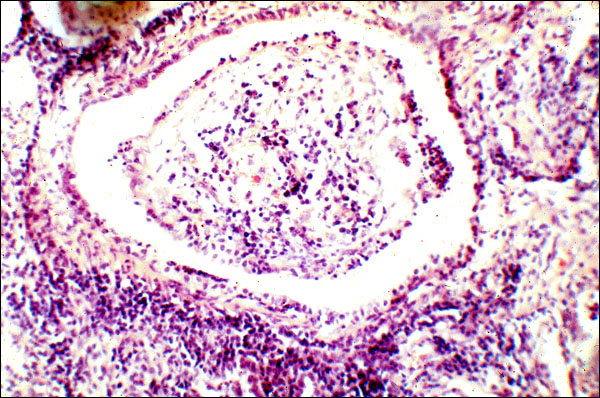

This slide is a photomicrograph of a section of lung afflicted with bronchiolitis obliterans. This is the result of chronic inflammation and is literally the plugging of bronchioles with fibrous connective tissue. Thus, fibrosis can just as well cause loss of function by adding fibrous connective tissue where it doesn't belong -- in this case, in an airway -- as by constriction.